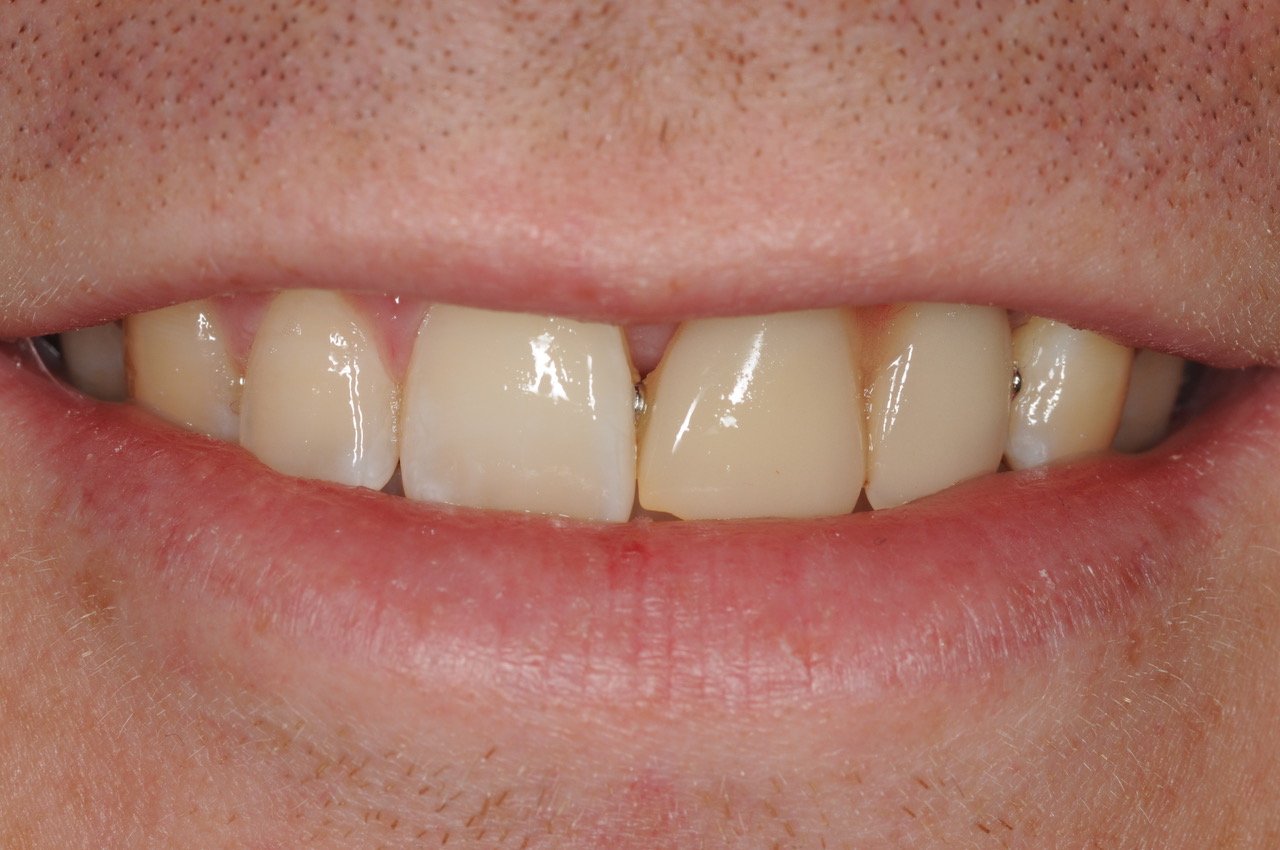

One restorative abutment was placed on the implant and then a 2-tooth cantilever bridge was placed on the abutment. The final result appears to be two teeth, but in fact, they are joined together as a bridge, and they are only supported by the one implant, which is in the central incisor position. This design is very functional and also easy for the patient to clean.

The final photographs reveal a functional and very aesthetic result, utilising a cantilever bridge. This type of bridge is very durable, and also saves treatment complexity and cost as only one implant and one restorative abutment are required, rather than two of each.